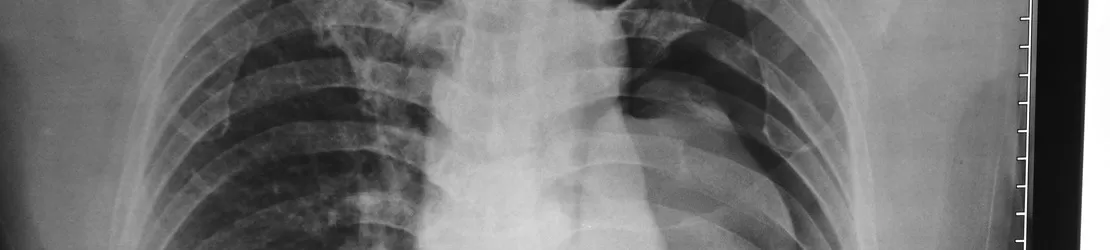

medic care studiaza o radiografie

Diagnosticare

Diagnosticarea unui pneumotorax implică, de obicei, o examinare fizică, o analiză a simptomelor și a istoricului medical și teste imagistice:

• examinarea fizică - medicul specialist pneumolog va asculta plămânii cu un stetoscop; în cazul unui pneumotorax, sunetele respiratorii pot fi diminuate sau absente în zona plămânului colapsat;

• radiografie toracică - acesta este cel mai frecvent test utilizat pentru a confirma un pneumotorax, care apare ca un spațiu liber, fără marcaje pulmonare, unde plămânul s-a prăbușit departe de peretele toracic;

• tomografie computerizată (CT) - aceasta va oferi o imagine detaliată a plămânilor și ajută la diagnosticarea unui pneumotorax care poate să nu fie vizibil la o radiografie toracică; de asemenea, poate contribui la determinarea cauzei dacă se datorează unei boli pulmonare subiacente;